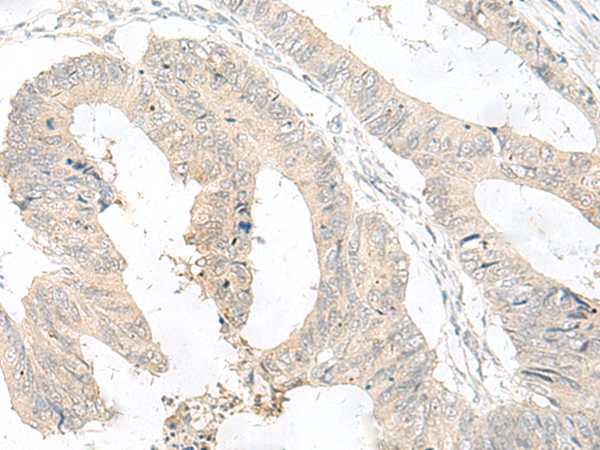

分类: 科研抗体货号: P13536别名: GRP; HSPC159应用: IHC反应种属: Human, Mouse